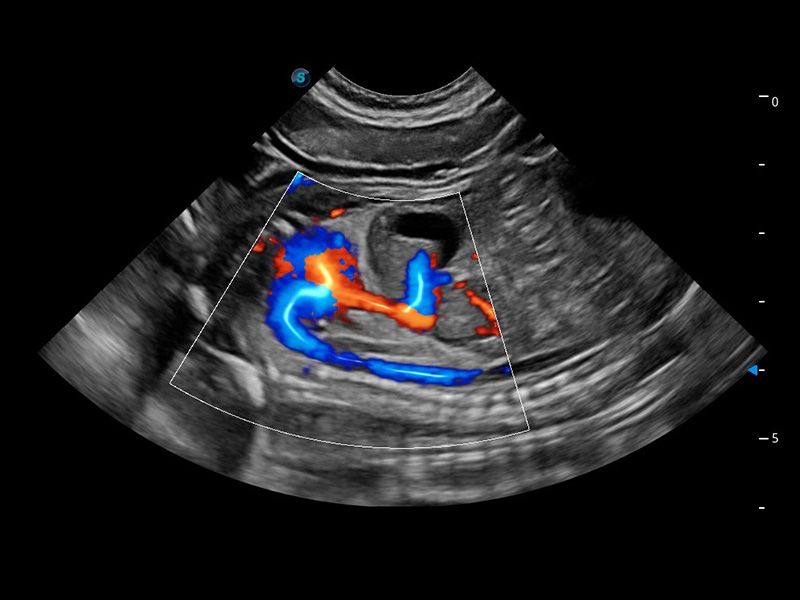

ProPet 60 作为一款高端台式动物超声设备,为动物医生的日常诊断提供了一系列贴合动物临床需求、解决临床实际问题的高级成像功能。凭借全系列高清探头,满足医生对腹部、心脏、生殖、浅表、肌骨等成像的所有需求,切实帮助您提升检查效率,提高诊断信心。

兽用彩色多普勒超声诊断系统

动物是人类最亲密的朋友和最值得信赖的伙伴。百老汇电子游戏官网也一直致力于探索动物专用的超声影像解决方案。 全新推出的ProPet系列,是百老汇电子游戏官网在动物超声影像智能化、专业化、精准化的一次跨越式革新。动物不能用言语来表述自己的不适,通过超声影像,ProPet系列搭建了动物医生与不同物种沟通的“桥梁”,为动物医生注入了“治愈之力”。